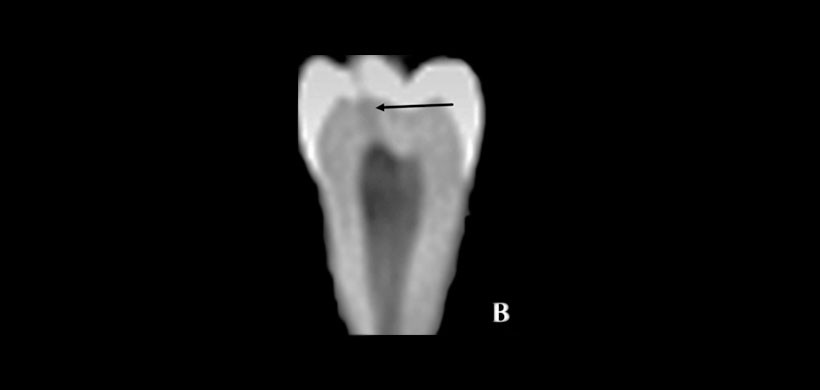

Para lo cual se utilizaron cuarenta y cuatro dientes con diferentes extensiones fisuras artificiales, creadas por exposición al nitrógeno líquido y después de agua caliente a 100 ° C. Posteriormente fueron sometidos a PR y CBCT. (Figura 1)

Para medir y registrar la profundidad de a grieta, se utilizó la microtomgrafia computarizada (miicro-CT), considerada como un examen relativamente más preciso que otros. La observaciones fueron realizadas por tres observadores, un estudiante graduado de endodoncia, un endodoncista y un radiólogo experimentado respectivamente, examinaron los resultados de PR y CBCT independientemente, y la presencia o ausencia de fisuras respectivamente. (Figura 2)